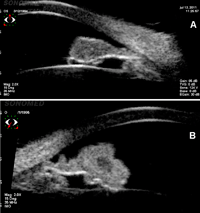

Figura 3). La BMU es un excelente medio de exploración de las estructuras angulares, lo que supone una gran ayuda para valorar el daño angular secundario a un traumatismo:

Figura 3. a) Subluxación de LIO con roce de la óptica con el epitelio pigmentario del iris. El paciente consultaba por visión borrosa y presentaba un mínimo Tyndall hemático. b y c) Corte longitudinal y transverso de háptico enclavado en el sulcus, produciendo varios cuadros de hemovítreos leves de repetición.